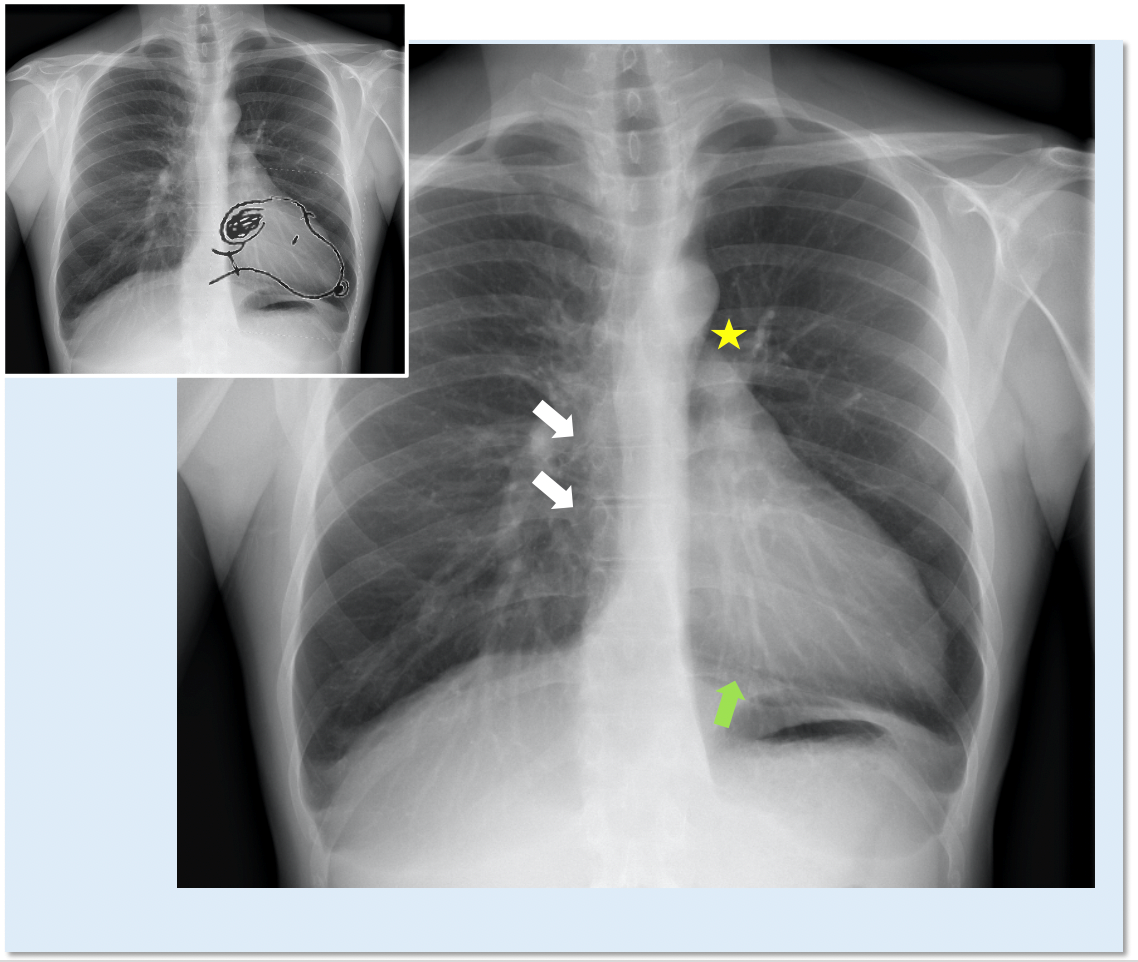

CXR

• Left CPA heart can shift posterior and left causing straightening and elongation of heart (levorotation and levoposition)

• "Snoopy" Sign

Indications for Echo

• Chest pain consistent with pericarditis or dissection

• Enlarged cardiac silhouette on chest x-ray